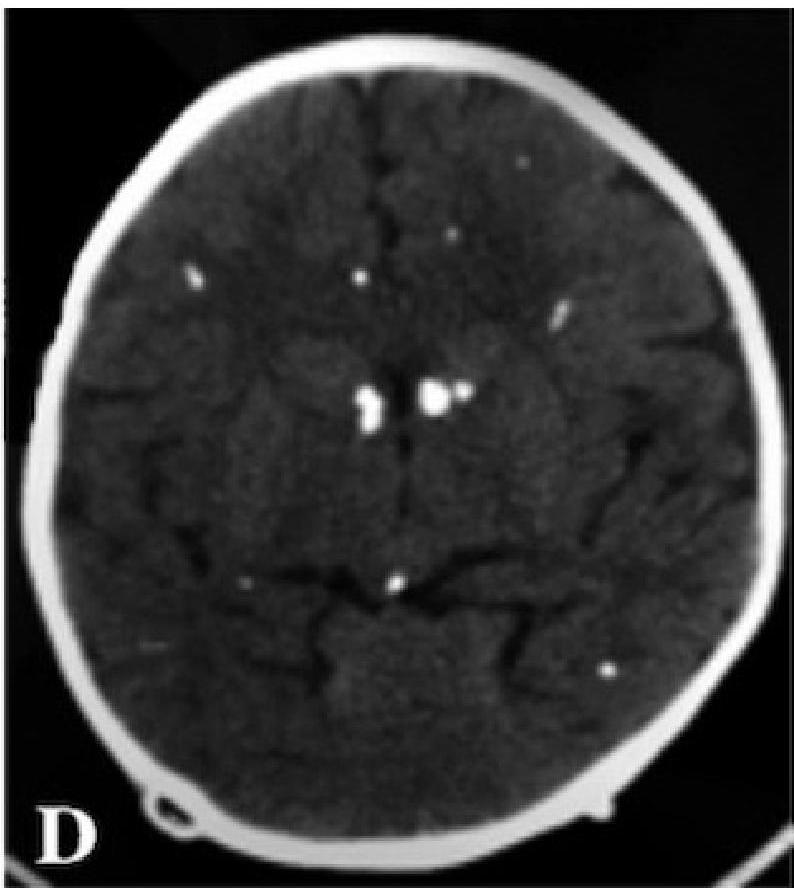

- Neurological: Microcephaly, Seizures, Intracranial calcifications (classically periventricular).

Ventriculomegaly and calcification of congenital CMV

- Imaging: Cranial ultrasound/CT → periventricular calcifications, ventriculomegaly.

Toxoplasmosis → diffuse intracranial calcifications.